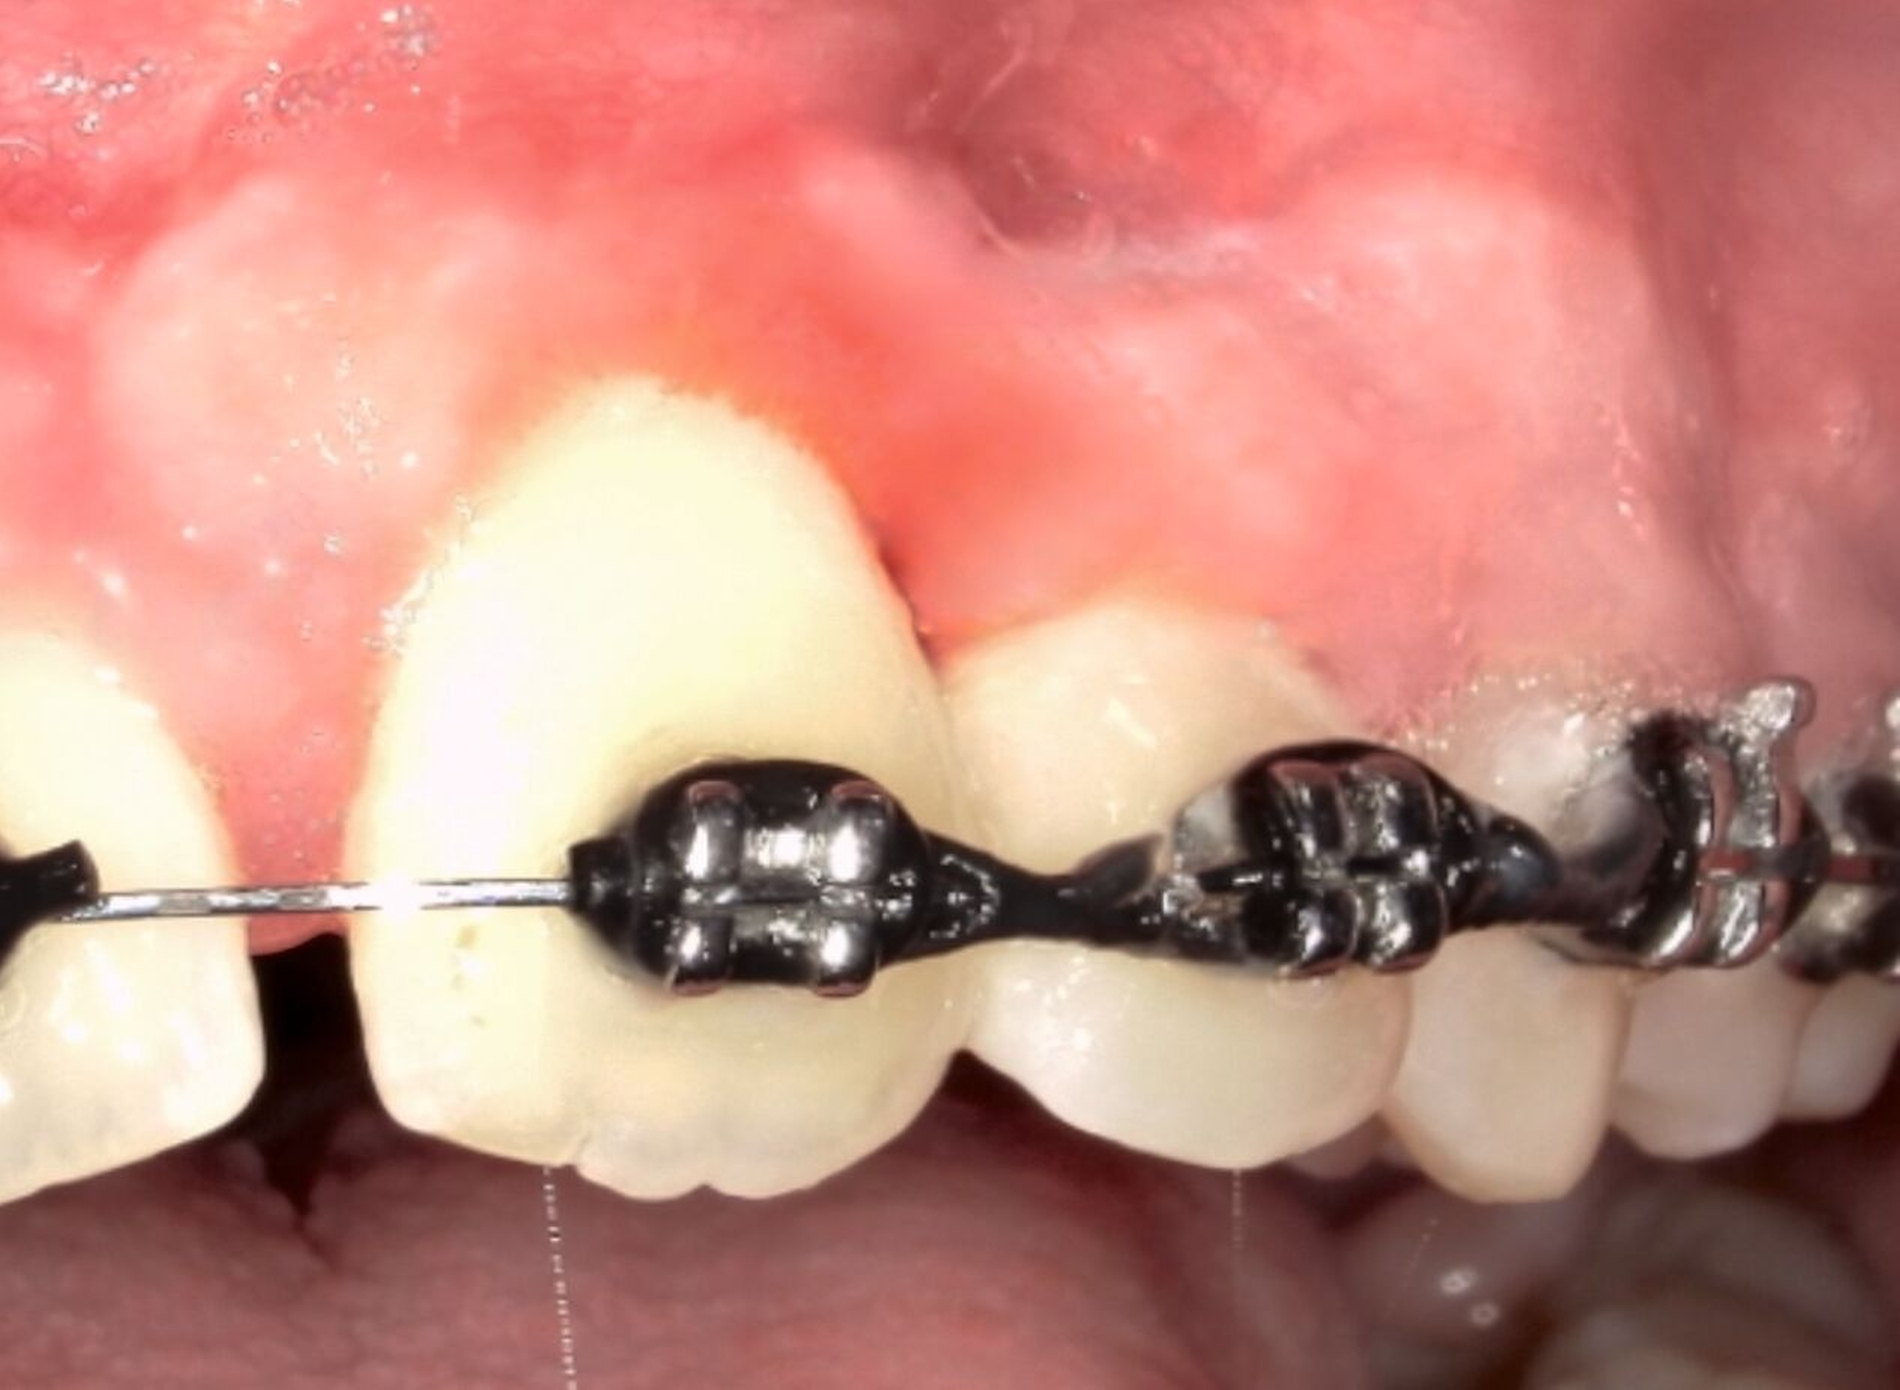

Die entstandene ossäre Kavität wurde mit einem Knochenersatzmaterial mit Kollagenzusatz aufgefüllt, und es wurde ein plastischer Wundverschluss durchgeführt (Abbildung 4). Das entnommene Gewebe wurde zur histopathologischen Untersuchung in die Pathologie der Universitätsmedizin Mainz eingesandt. Histologisch zeigte sich ein zellarmes, bindegewebiges Stroma mit strangförmig angeordneten Zellen odontogenen Epithels.

Im Zentrum der soliden Epithelansammlungen ließen sich drüsenähnliche Strukturen erkennen. Zudem wurden kleinere Ablagerungen beobachtet, die als dentinähnliche Hartgewebsablagerungen interpretiert wurden (Abbildung 5). Auf dieser Grundlage wurde die Diagnose eines adenomatoiden odontogenen Tumors (AOT) gestellt, welche durch das Institut für Pathologie der Universität Erlangen konsiliarisch bestätigt wurde. Der Patient befindet sich in der Nachsorge (Abbildung 6). Die angrenzenden Zähne sind weiterhin pulpavital und die kieferorthopädische Behandlung wird weitergeführt.